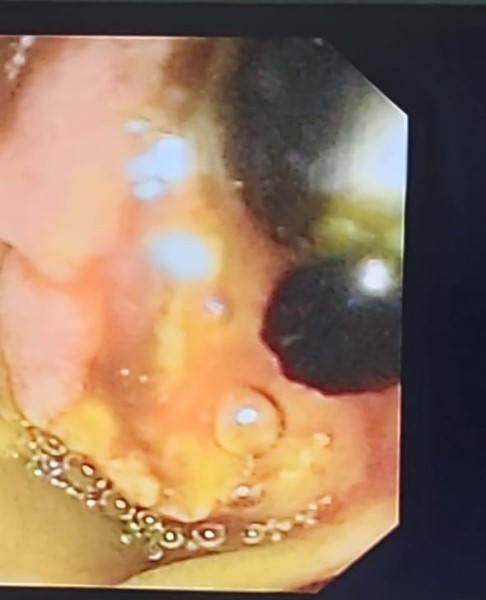

Gastroenterology & Hepatology

Surgery Photos